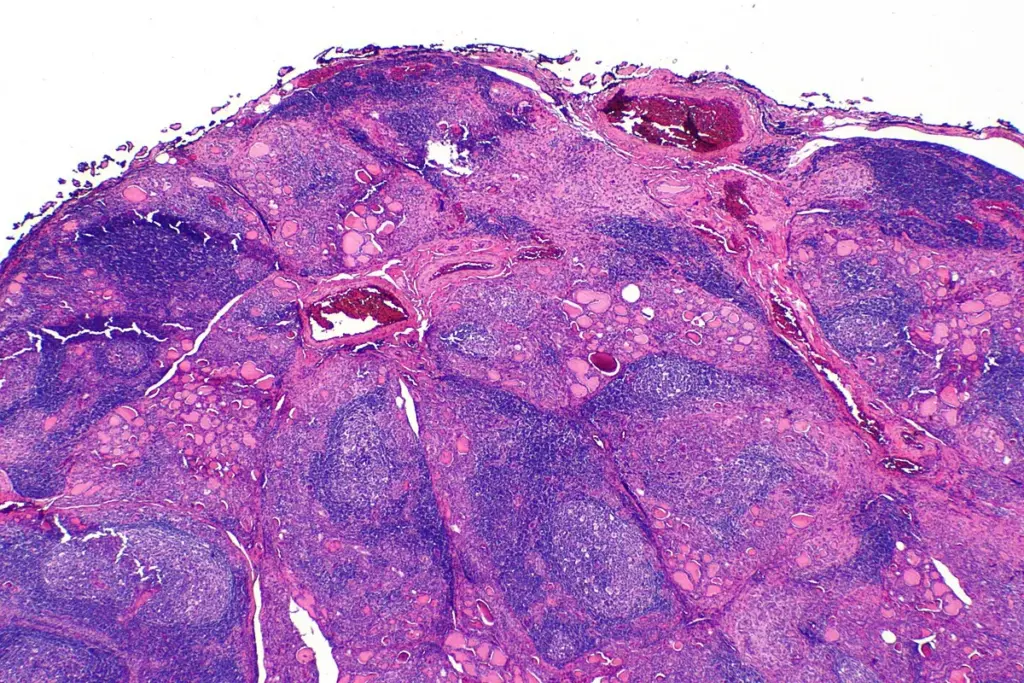

In some clinical cases, if a suspicious nodule is found during the ultrasound, a fine needle aspiration biopsy may be performed.

• A very thin needle is used to collect a small sample of cells.

• A pathologist examines the cells to rule out malignancy or other types of thyroiditis.

• It helps confirm the presence of lymphocytes within the gland tissue.

While not required for every diagnosis, this procedure is a hallmark of the thorough care provided at Liv Hospital, ensuring that no underlying issues are missed during the evaluation of the immune-damaged tissue.